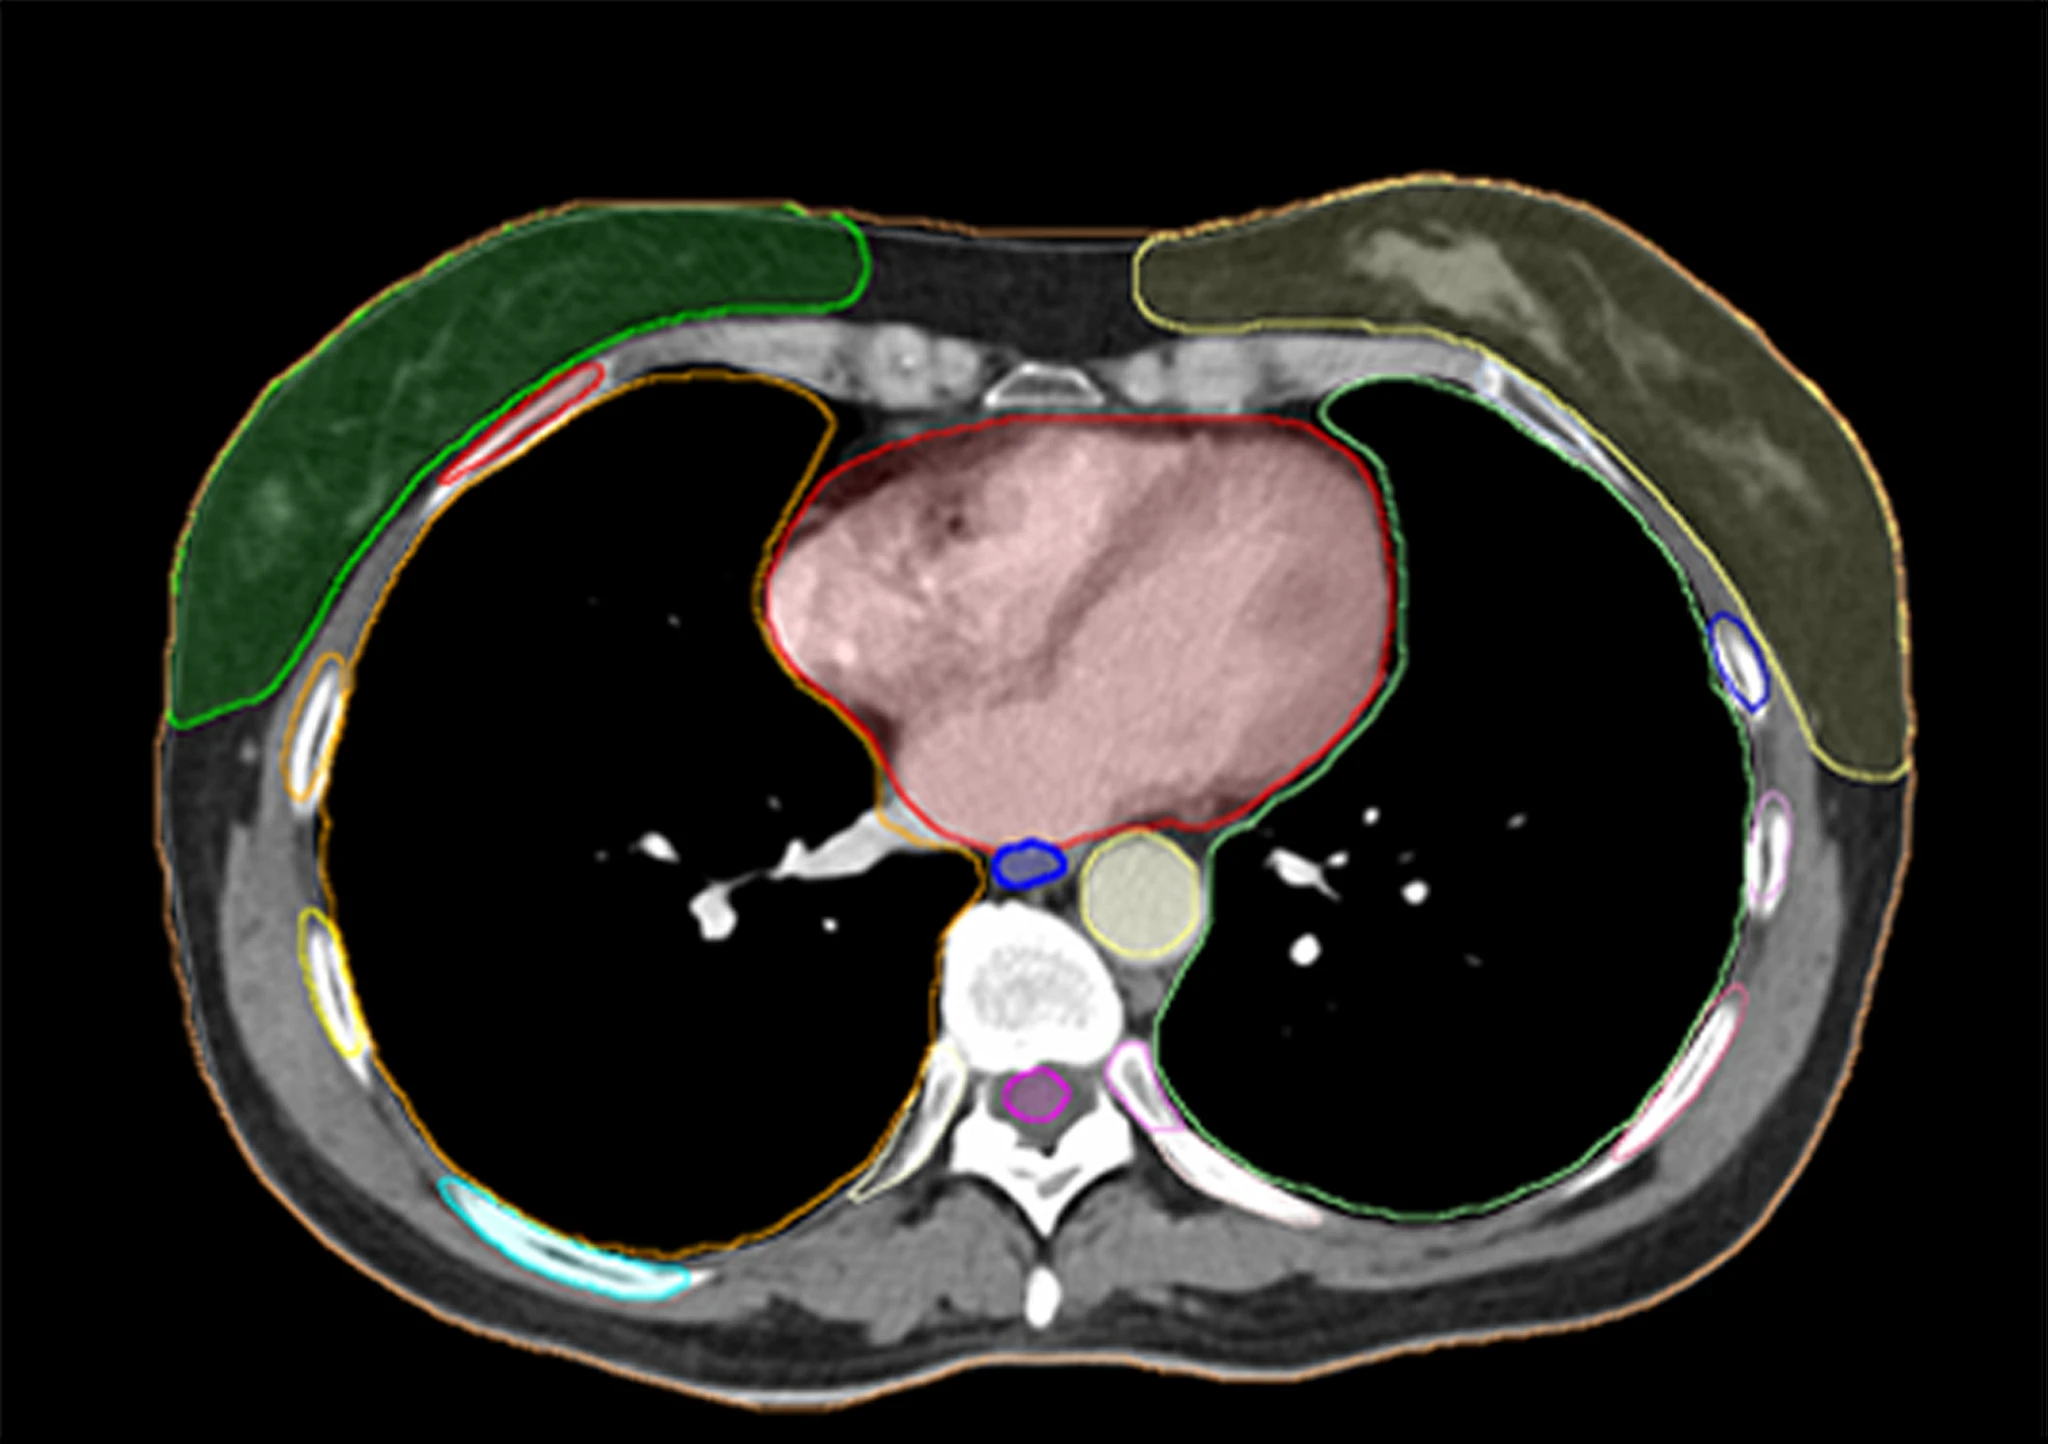

Fully integrated with Varian technology, the optical surface monitoring system is a 3D tracking solution that consists of three camera units set up around the patient. Instead of localizing patients based on three points in space with lasers and tattoos, OSMS can localize patients by tracking 3,000 points on the surface of the patient’s body, without using ionizing radiation, implanting fiducials, or making marks on the skin. If a patient’s position changes and is outside the thresholds that have been predefined by the clinical team, the OSMS stops the beam using an automatic beam hold function.

Currently, about 80 to 90 percent of all patients receiving radiotherapy at Cone Health are treated with OSMS, including virtually 100 percent of the SBRT patients. The Cone Health team commonly uses OSMS as a secondary system to cone-beam CT image guidance when monitoring patients because it allows them to see patients’ positions in real-time, ensuring that they are in the right position throughout the treatment. According to Wiant, his clinical team is in the process of adopting an OSMS-based process for treating all SRS patients.

Certain patients – such as those being treated for breast cancer, superficial tumors or those who are receiving high dose treatments to areas like the liver, spine, lung and brain – are treated with OSMS for patient verification, setup, and monitoring while all others are generally treated using OSMS for patient verification and monitoring.